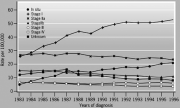

| 11:58, 7 בספטמבר 2012 | TMNgraph412.png (קובץ) |  |

340 קילו־בייטים | Motyk | 1 | |